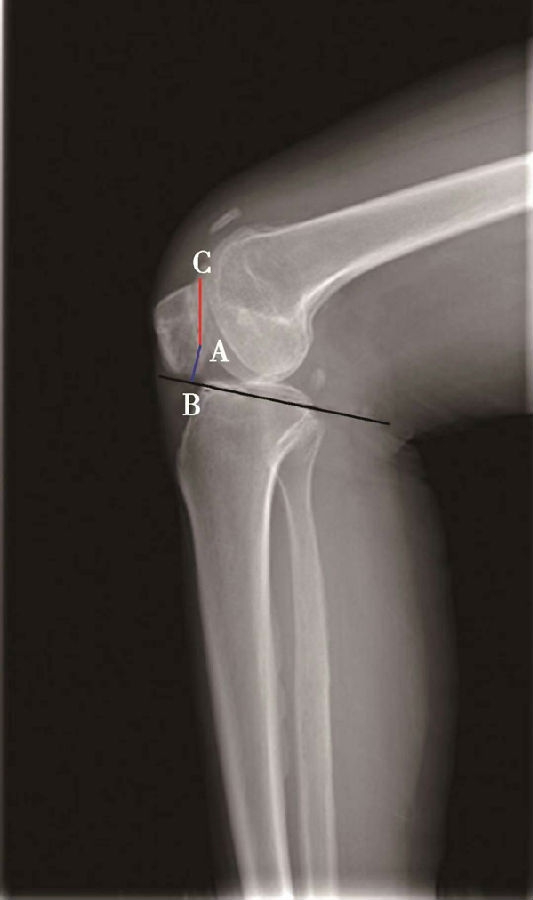

(3)BlackBurne-Peel指数>1.0提示高位髌骨(图8),<0.5提示低位髌骨(图9)。

如图示:AB是髌骨关节面最低点到胫骨平台延长线的垂直距离。AC是髌骨关节面的长度。BlackBurne-Peel指数=AB/AC(图7)。

该方法同样可以评估胫骨结节移位或胫骨高位截骨术后的髌骨高度。但是也有其缺点:①部分患者的髌骨形态异常,难以分辨髌骨关节面的长度;②标记胫骨平台的延长线也需要较高的精度;③胫骨平台后倾角越大,可能导致髌骨关节面的最低点到胫骨平台的延长线的垂直距离越短。因此,如果手术改变了胫骨平台的后倾角度,则会使BlackBurne-Peel指数出现偏差。

图7 BlackBurne-Peel指数=AB/AC=0.80,为正常髌骨高度